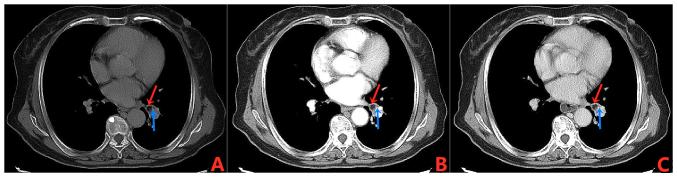

Endobronchial lipoma (EL) is a rare benign lung tumor, and its incidence rate only accounts for a tiny proportion of all lung tumors. EL has non-specific clinical symptoms and signs, and chest computed tomography is helpful in diagnosis. When fat density nodules are found in the bronchial lumen with no enhancement, EL should be considered. Once this disease is diagnosed, bronchoscopic intervention therapy is the first choice for treatment, and patients generally have a good prognosis. The present report describes the diagnosis and treatment processes of a patient with EL. The patient sought medical attention due to recurrent fever, cough and white sputum for >1 month. The chest CT revealed a hypodensity nodule at the bronchial opening of the basal segment of the lower lobe of the left lung, with the margins showing foci of punctate calcification. The patient underwent a bronchoscopy and the pathological diagnosis was EL. In the present study, a literature review analysis is also included to provide a reference for the diagnosis and treatment of this disease.

支气管内脂肪瘤(EL)是一种罕见的良性肺肿瘤,其发病率仅占所有肺肿瘤的极小比例。EL具有非特异性的临床症状和体征,胸部计算机断层扫描有助于诊断。当在支气管腔内发现脂肪密度结节且无强化时,应考虑EL。一旦确诊此病,支气管镜介入治疗是首选治疗方法,患者总体预后良好。本报告描述了一名EL患者的诊断和治疗过程。该患者因反复发热、咳嗽及咳白色痰1个月以上前来就医。胸部CT显示左肺下叶基底段支气管开口处有一个低密度结节,边缘可见点状钙化灶。患者接受了支气管镜检查,病理诊断为EL。本研究还纳入了文献综述分析,为该病的诊断和治疗提供参考。